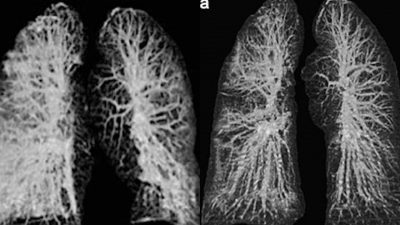

Los especialistas del Instituto Nacional de Enfermedades Infecciosas en Roma estudiaron los cuerpos de los pacientes de 65 y 67 años y detectaron, mediante rayos-X y tomografías computarizadas, un gran deterioro en la función de los pulmones.

Cuando coronavirus ataca los pulmones, provoca una inflamación en las membranas mucosas, lo genera un daño en los alvéolos pulmonares, que tienen que trabajar más para suministrar oxígeno a la sangre que circula por todo el cuerpo y eliminar el dióxido de carbono para que se pueda exhalar. La inflamación y el daño al flujo de oxígeno pueden causar que dichas áreas en los pulmones se llenen de fluido, pus y células muertas.